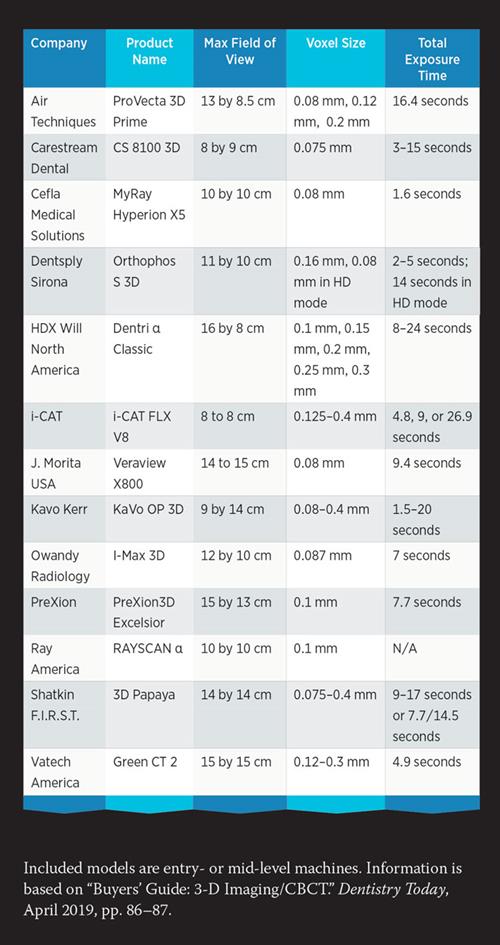

CBCT system costs (2026 range: $68k–$142k) are determined by engineering trade-offs in three critical subsystems:

Cost variance stems from anode heat capacity (kHU), detector quantum efficiency (DQE), and spatial resolution (lp/mm):

- High-End ($120k+): Tungsten-rhenium anodes (150kHU capacity) with CsI scintillators (DQE ≥85% at 0.5 lp/mm). Enables 70μm voxel resolution at 4.7s scan time without motion artifacts. Cost premium: 32% over mid-tier for 40% higher thermal tolerance.

- Mid-Tier ($85k–$110k): Standard tungsten anodes (90kHU) with amorphous silicon detectors (DQE 72–78%). Resolution limited to 120μm voxels due to modulation transfer function (MTF) decay at high frequencies.